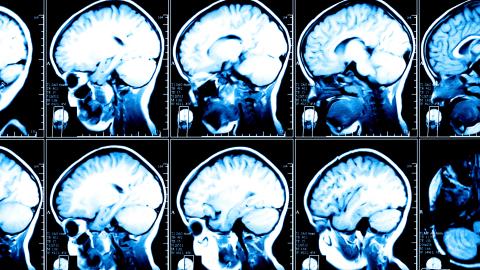

The Brain Scan Image and the Dangers of Brain Porn

The brain scan may be the iconic scientific image of the early 21st century. Not only does the image represent our growing understanding of the physical processes in the brain, it represents our willingness to accept neuroscientific explanations for just about anything. “Neuroscience is frequently used to discuss psychopathology in particular, with 36% of ‘neuroscience’ mentions in mainstream articles referring to it. Psychopathology can include anything from dementia, ADHD, and schizophrenia to eating disorders, personality disorders, addiction, depression, and anxiety.”

The danger in explaining aberrant behavior in terms of miscued biology is that essential human elements, such as sympathy and free choice, are removed from the equation. Alcoholism, as a physical disease, helps to legitimate treatment resources but it can also imply that alcoholics are biologically abnormal. By making biological correlates essential to understanding of psychological illness, we often fall victim to the naturalistic fallacy, that what is right is what is biologically prescribed. Brain scans can give the illusion of scientific evidence even when they do not add any substantial information.